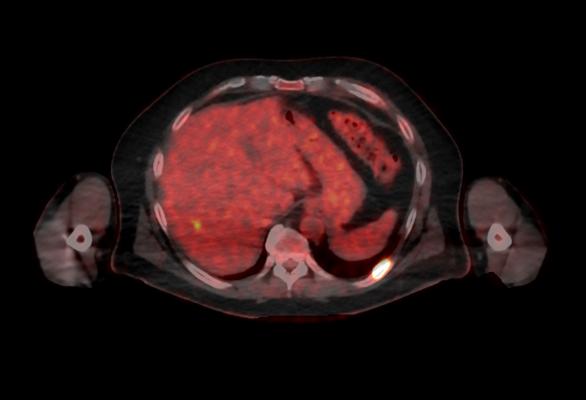

October 5, 2016 — GE Healthcare recently announced U.S. Food and Drug Administration (FDA) 510(k) clearance of its Discovery MI digital positron emission tomography (PET)/computed tomography (CT) system and shared a series of first clinical images. Built with technology allowing significantly better small lesion detectability, Discovery MI can help clinicians in their efforts to diagnose and stage disease earlier.

Discovery MI was created to help clinicians achieve their primary goal of diagnosing and staging disease earlier and to better guide their treatment strategies. It also enables more compelling research with more novel, faster decaying tracers. A key component in delivering these desired outcomes is Discovery MI’s LightBurst Digital Detector. This detector delivers up to two times improvement in volumetric resolution, enabling small lesion detectability, and has the highest NEMA sensitivity of any time-of-flight (TOF)/PET system in the industry, according to GE.

Discovery MI may also enhance clinicians’ diagnostic service offerings in oncology and expand PET’s impact in neurology, cardiology and beyond. These expanded capabilities are enabled by the ability to increase low-yield tracer capability with protocols that reduce dose by up to 50 percent, allowing clinicians to pursue research without impacting image quality.